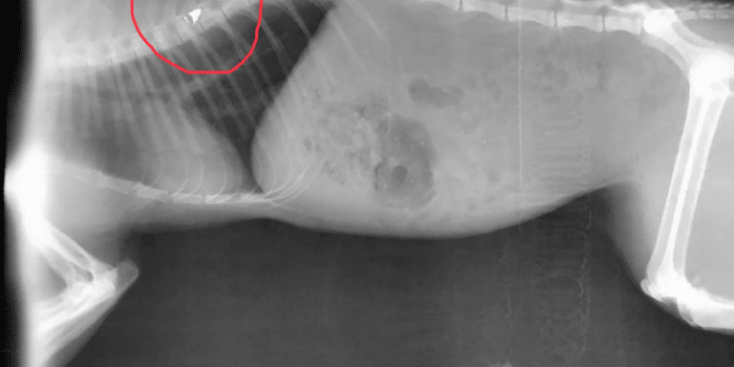

Το άτυχο ζώο πυροβολήθηκε από τον δράστη με αεροβόλο όπλο, πριν από δύο μέρες. Όπως αναφέρει το Star Κεντρικής Ελλάδος, σύμφωνα με την απόφαση, στην ποινή φυλάκισης προστίθεται και χρηματικό πρόστιμο (σύμφωνα με τον νέο Κώδικα) 360 μονάδες x 10 ευρώ ημερησίως (3.600 ευρώ που διπλασιάζονται).